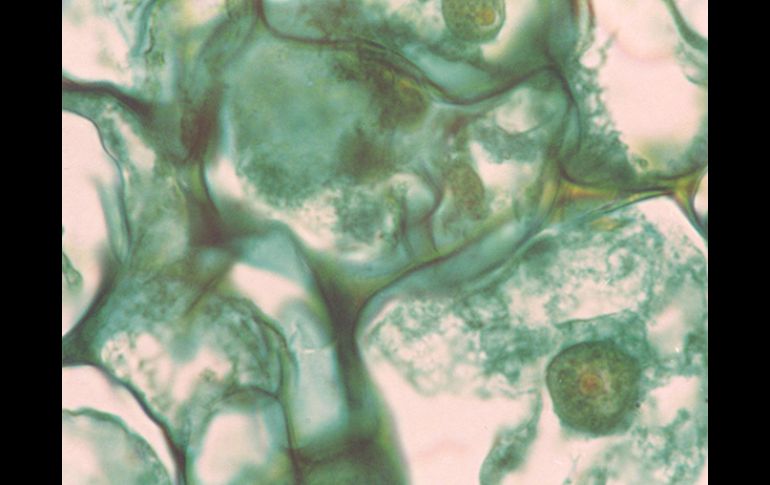

Tecnología | 28.5 por ciento de la población mexicana presenta en su vida un trastorno mental Buscan en árbol mexicano opciones para el tratamiento psiquiátrico La salud mental es un factor preponderante para el desarrollo integral de cualquier persona Por: EL INFORMADOR 2 de noviembre de 2010 - 20:02 hs Trabajan en la obtención de los metabolitos honokiol y magnolol a partir de cultivos celulares. ID / CIUDAD DE MÉXICO (02/NOV/2010).- La salud mental es un factor preponderante para el desarrollo integral de cualquier persona. No obstante, esta condición se ha visto afectada en los últimos años, pues enfermedades como depresión, ansiedad, esquizofrenia y todo tipo de fobias se han vuelto más comunes. De acuerdo con la Encuesta Nacional de Epidemiología Psiquiátrica (ENEP), 28.5 por ciento de la población mexicana presenta en su vida un trastorno mental. Con el propósito de buscar fármacos alternativos que ayuden al tratamiento de estas personas, la doctora Irma Fabiola Domínguez Avilés, del Centro de Investigación Biomédica de Oriente, del Instituto Mexicano del Seguro Social (Cibior-IMSS Puebla) trabaja en la obtención de los metabolitos honokiol y magnolol a partir de cultivos celulares del árbol mexicano Magnolia dealbata Zucc. A decir de la titular del proyecto, estos compuestos son los principios activos de extractos estandarizados y vendidos ampliamente para el tratamiento de trastornos del sistema nervioso central, como la ansiedad. Motivo por el cual China y Japón tienen grandes plantíos de árboles magnoliaceaes para abastecer al mercado mundial. Asimismo, explicó que, en condiciones de estrés, el árbol produce estos compuestos como un mecanismo de sobrevivencia a la sequía; así como para defenderse de los insectos. Por otro lado, destacó que, en una búsqueda química de estos metabolitos, encontraron que el árbol mexicano Magnolia dealbata Zucc produce mayores cantidades que la especie asiática. Agregó que la especie dealbata es endémica de México, pues únicamente crece en algunos puntos de Veracruz; y está en peligro de extinción debido a la baja germinación de las semillas y a que su corteza es empleada para fabricar vigas. Con la intención de no afectar al medio ambiente, el equipo de trabajo de ese centro de investigación decidió aprovechar la totipotencialidad celular (capacidad de dar origen a varios tipos de células) y producir honokiol y magnolol en el laboratorio. Estos compuestos fueron obtenidos en un sistema de cultivo in vitro con nutrientes y hormonas que permiten el crecimiento de las células sin necesidad de reproducción sexual. “Al estar en contacto con el medio de cultivo, diseñado previamente, las células comenzaron a sobreproducirse de forma acelerada; mientras que con el movimiento de nutrientes se logró que éstas iniciaran la producción de los metabolitos”, expuso. Posteriormente, mediante cromatografía de líquidos de alta resolución (técnica que permite identificar y separar los distintos componentes de una solución por la absorción selectiva de los constituyentes) se monitoreó la producción de metabolitos a partir de las células; así como los nutrientes necesarios para que esto suceda. Domínguez Avilés explicó que este análisis continuo les permite establecer bioprocesos, o procesos de producción, que faciliten el escalamiento a un biorreactor para las pruebas clínicas de los compuestos. A este respecto explicó que tras ser sometidos a pruebas en animales, los metabolitos obtenidos reportan actividad anticonvulsiva y ansiolítica; además de que no producen sedación ni hipnosis. Resultados que los diferencian de los fármacos empleados con frecuencia en el tratamiento de trastornos de ansiedad. Además, con este bioproceso in vitro de 30 días, produjeron 300 por ciento más de honokiol y magnolol que en las plantas silvestres. Cabe señalar que este proyecto de investigación, financiado por el Fondo Sectorial de Investigación en Salud y Seguridad Social SSA/IMSS/ISSSTE-Conacyt, es realizado en colaboración con la Unidad de Investigación en Enfermedades Neurológicas del Centro Médico Nacional Siglo XXI, del IMSS, y el Instituto Nacional de Psiquiatría Ramón de la Fuente Muñiz. Con información de la Agencia ID. Temas Investigación científica Ciencia médica Enfermedades Lee También INAPAM: ¿Cómo solicitar un turno para consulta médica gratuita? Investigación de Rancho Izaguirre no está archivada; 12 funcionarios están involucrados Nobel de Química premia el desarrollo de estructuras metal-orgánicas Nobel de Física para Clarke, Devoret y Martinis por descubrimiento sobre fenómenos cuánticos Recibe las últimas noticias en tu e-mail Todo lo que necesitas saber para comenzar tu día Registrarse implica aceptar los Términos y Condiciones